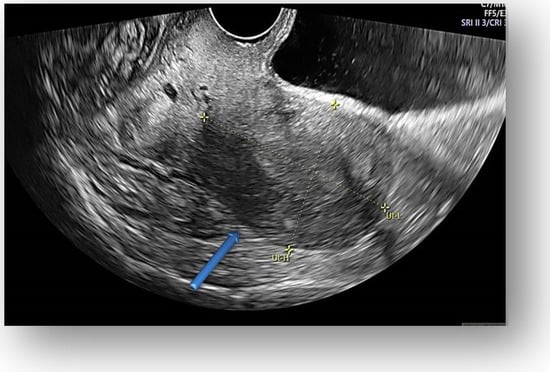

Figure 3.

Transvaginal ultrasound showed uterine body with normal endometrium.